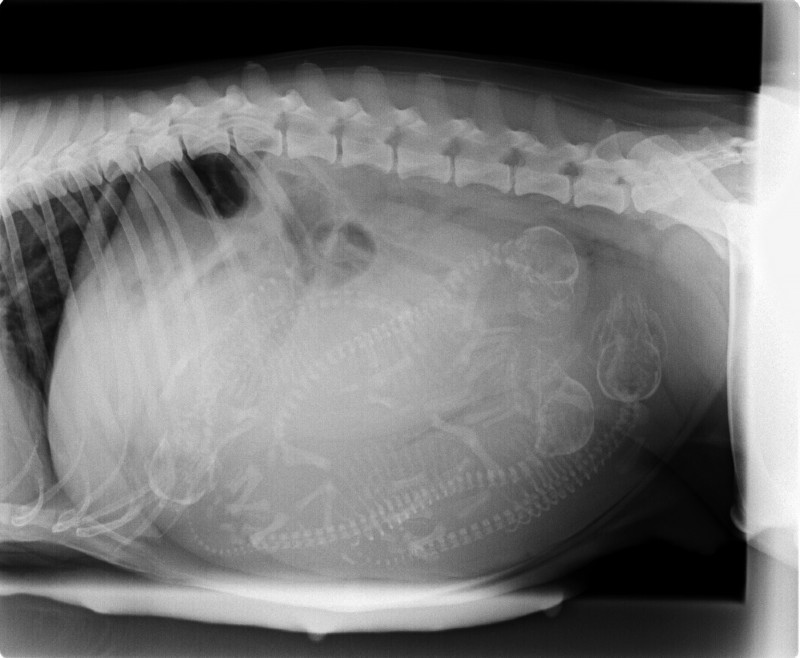

• Trächtigkeitsuntersuchung mittels Ultraschall

• Geburtshilfe und Welpenbetreuung

• Kaiserschnitte unter schonender Inhalationsnarkose